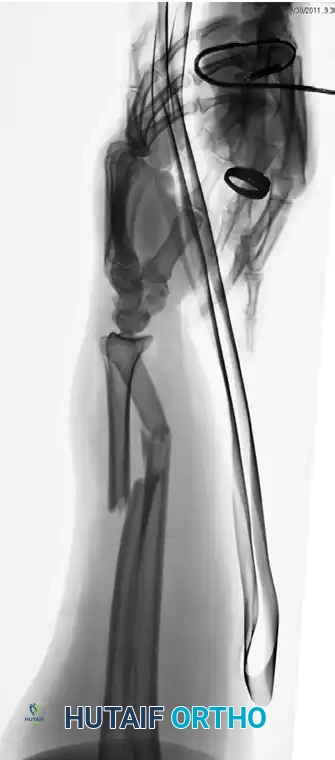

Case Example: Essex-Lopresti Reconstruction

The following sequence demonstrates the complex management of an Essex-Lopresti injury complicated by radial shortening.

Figure 57-80A: Initial presentation showing radial head fracture and longitudinal instability.

Figure 57-80B: Associated DRUJ disruption and ulnar variance.

Figure 57-80C: Attempted initial stabilization.

Figure 57-80D: Progressive proximal migration of the radius due to unrecognized or inadequately treated IOM disruption.

Figure 57-80E: Application of an external fixator; however, profound radial shortening and ulnocarpal impaction remain evident.

Figure 57-80F: Definitive revision surgery utilizing a radial head prosthesis to restore the proximal buttress and reestablish anatomical radial length.